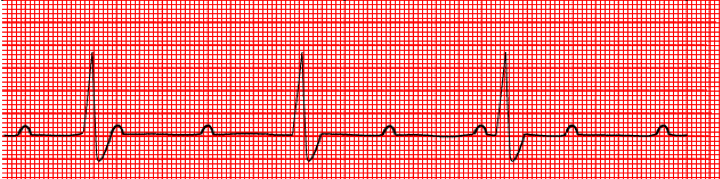

Identify the rhythm.

What is one priority intervention?

Third degree heart block, rate of 30 bpm.

Pacemaker indicated.